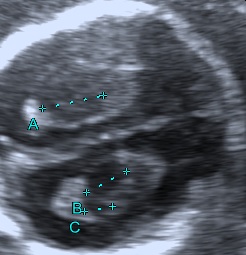

In the second trimester choroid plexus cysts are found in 1–3% of normal fetuses and in 30–50% of trisomy 18 fetuses (Dagklis T. et al., 2008).

The presence of choroid plexus cysts increases the risk for aneuploidy, mainly trisomy 18. In the majority of cases, the final risk will remain small, but will increase as maternal age increases (Chitty L. et al., 1998).